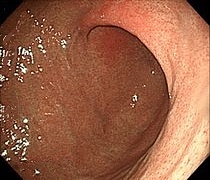

胃がんの精査は主に上部消化管X線検査(胃透視)と上部消化管内視鏡検査(胃カメラ)があります。当院では早期発見により有効な検査である内視鏡検査(胃カメラ)を主に行っています。 がんを疑う病変に対しては、内視鏡で観察しながら鉗子(かんし)と呼ばれる器具で病変の一部を採取(生検)して、顕微鏡による病理診断を行い、がんの有無を調べます。

早期胃がん

(NBI画像)